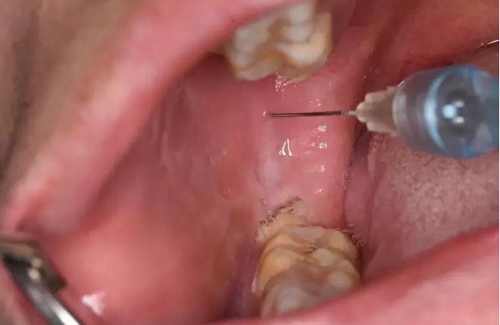

圖4.行下牙槽神經(jīng)阻滯麻醉